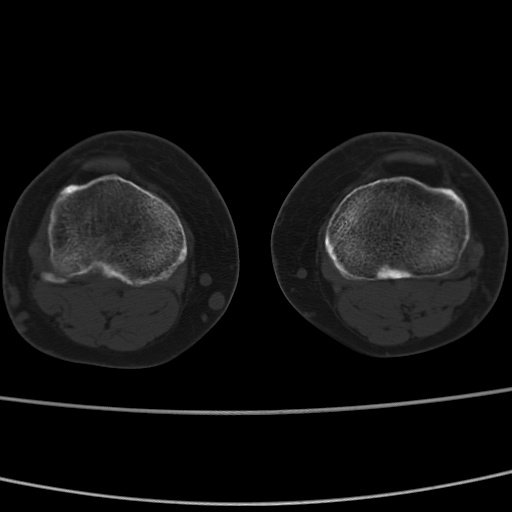

女性,50岁。【请提供患者临床症状体征】

右膝关节退行性改变,关节游离鼠。

右膝关节退行性改变,滑膜黏液囊钙/骨化并游离。